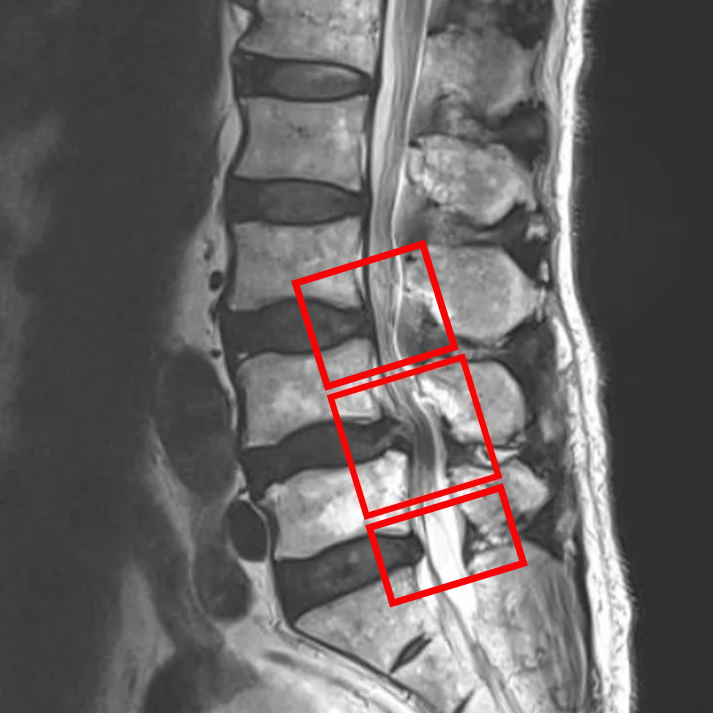

По данным МРТ и результатам осмотра пациента выявлен стеноз позвоночного канала L4/L5, а также дегенерация межпозвоночных дисков L3/L4, L5/S1.

Симптомы по 10-балльной шкале (0 – отсутствие симптомов, 10 – сильные боли/онемение):

– боли в пояснице: 4;

– боли в ногах: 1;

– онемение в ногах: 2;

– боли в ягодицах: 5.